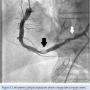

A 58-year-old male presented for cardiac evaluation prior to renal transplantation. He complained of dyspnea on exertion and fatigue. He had a history of hypertension, hyperlipidemia, diabetes mellitus, end-stage renal disease and stroke. Medications included aspirin, diltiazem, carvedilol, atorvastatin and losartan. Cardiovascular exam was unremarkable. An echocardiogram showed normal left ventricular systolic function. An EKG was normal. An exercise nuclear stress test was stopped in the 6th minute of standard Bruce protocol due to fatigue and dyspnea. In the inferolateral leads, 2 mm ST depressions were noted, with a myocardial perfusion study showing a medium-sized inferior infarct with peri-infarct ischemia. Coronary angiogram revealed mild to moderate disease in the left system. The RCA was dominant, with a 99% mid stenosis followed by a 60% distal lesion (Figure 7). Left to right collaterals were noted. The RCA was severely calcified and tortuous with a downward take-off ostium (Figure 7). An 8 Fr multipurpose guide catheter was inserted through a 45 cm, 8 Fr femoral sheath. A BMW wire tip would not progress beyond the mid lesion, with the guide catheter disengagement from the RCA ostium just by pushing the wire. At this point, a telescopic system utilizing an 8 Fr and a 5.5 Fr GuideLiner was assembled outside the patient and advanced to the mid RCA, as detailed above. The BMW wire could then be advanced to the distal vessel without difficulty. After pre-dilating the mid RCA with a noncompliant balloon, the 5.5 Fr GuideLiner was advanced over the balloon beyond this lesion. A 4 x 28 mm Xience stent was advanced and “desheathed” off the GuideLiner. After stent deployment, a good final result was obtained. The patient was discharged home the following day and he remains asymptomatic.

proximal 100% occlusion of the LAD, and 70% proximal stenosis of the OM. All bypass grafts were patent. CTO PCI of the RCA was begun with an 8 Fr, 45 cm sheath via the femoral artery and Amplatz left 0.75 8 Fr guide catheter. A Pilot 200 guidewire (Abbott Vascular) was used to traverse the proximal cap and MiracleBros 6 wire (Asahi Intecc) was needed for distal cap crossing. An attempt at crossing the proximal cap with a small balloon was unsuccessful due to inadequate support. A similar telescopic system was used, as described in Case 1. Once an 8 Fr GuideLiner with a 6 Fr GuideLiner extension was inserted into the proximal RCA, the balloon crossing was relatively easy (Figure 5). PCI was concluded with a good result (Figure 6) and the patient was asymptomatic afterwards.